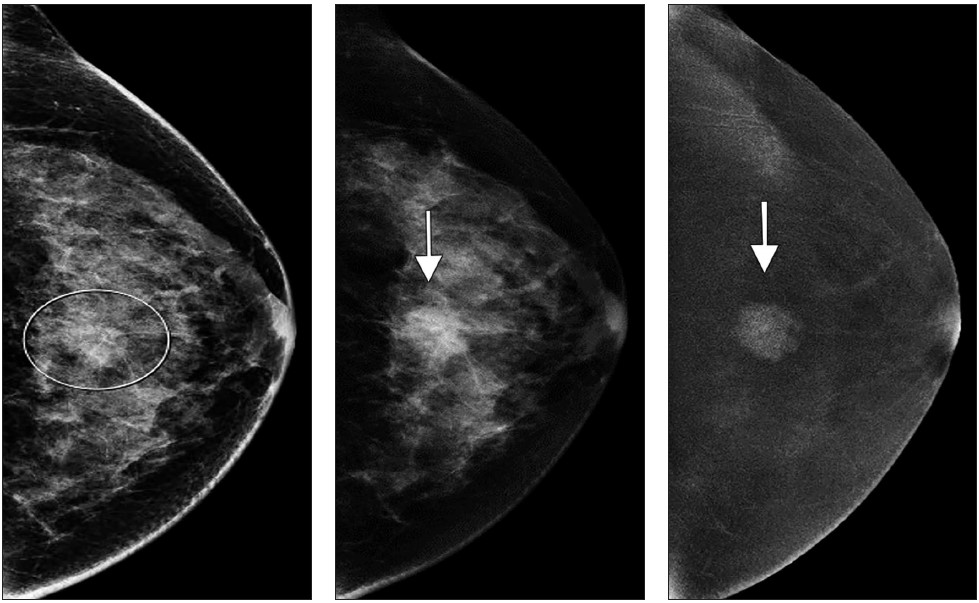

As of this writing, CEM has been approved by the FDA only as a diagnostic examination. For this reason, imaging practices are primarily using CEM as an alternative to MRI, when MRI cannot be performed. CEM is also used as a problem-solving tool in cases of known or suspected lesions. It is used in cases of recalls from screening; breast cancer staging (Fig. 1); evaluation of symptomatic breasts; troubleshooting complicated mammographic and ultrasound imaging, although this is rare; and treatment response to neoadjuvant chemotherapy. Some institutions are using CEM for supplemental breast cancer screening of patients who cannot undergo MRI, have dense breast tissue, or need additional screening.